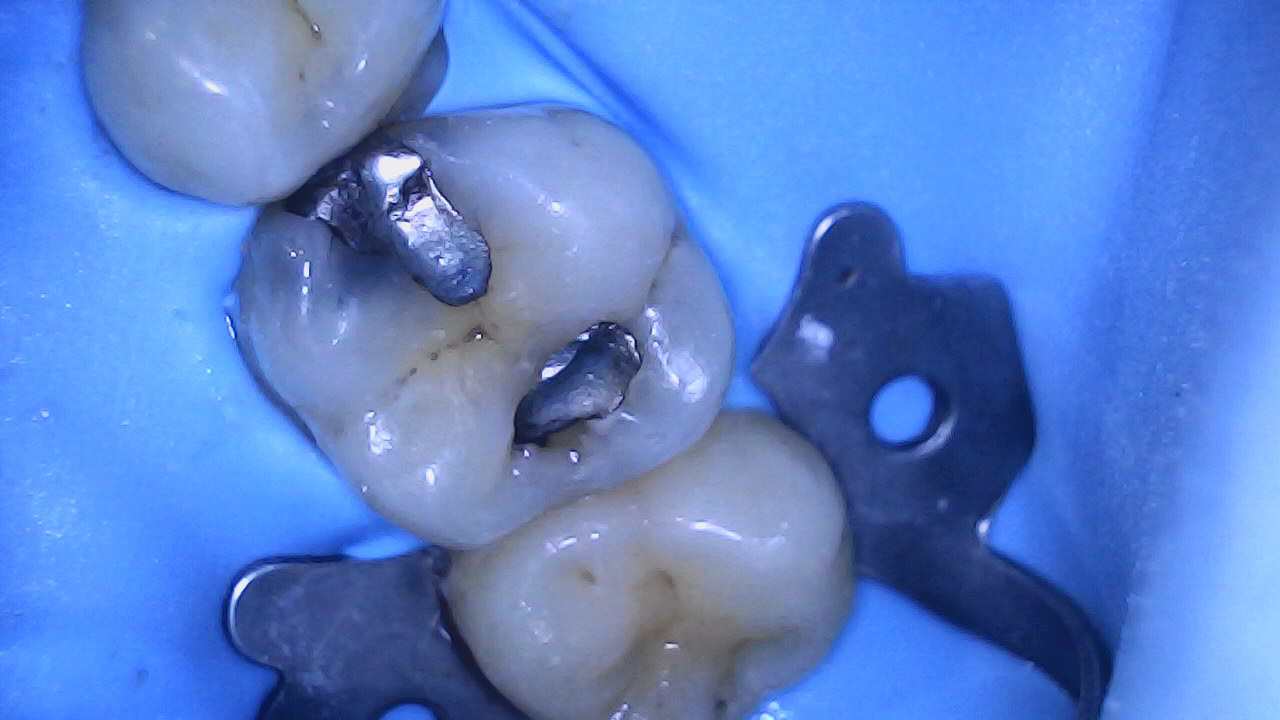

Amalgam + caries removal

Selective caries removal with help from caries dye